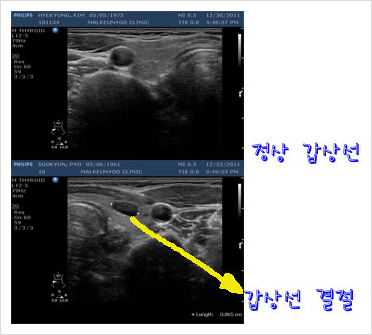

갑상선 결절은 우리가 눈으로 확인할 정도로 커지면 목 주위가 붉게 보일 수도 있다고 한다.실제로 이렇게 눈에 보이거나 만지는 결절은 5% 정도밖에 되지 않는다.그런데 최근에는 갑상선 초음파를 많이 하기 때문에 만져지지 않는 작은 결절도 많이 발견되는 추세다.

갑상선류(갑상선결절) 자각증상 혹이 커지고 있는 경우에는 자각할 수 있는 증상이 나타나기도 한다.최근에는 갑상선 결절이 너무 커져 발견되는 경우는 극히 드물어져 그 전 단계에서 초음파 검사에서 많이 발견되는 편이다.만지거나 밖으로 튀어나오는 혹과 달리 구별이 안 되는 초기 무증상 단계에서 초음파 검사에서 많이 발견되고 있다.

갑상선류(갑상선결절) 세포검사 미세침지세포검사 정확한 의학용어로는 ‘미세침지세포검사’라고 하며 갑상선결절이 발견될 경우 이것이 확실하게 암이 아닌지 확인하는 검사법이다.수술을 해서 확인하기는 어려우므로 초음파 검사를 하면서 가는 주사 바늘을 혹시 부위에 넣어 세포를 흡입, 즉 흡입한 후 이를 현미경으로 관찰하는 검사를 말한다.